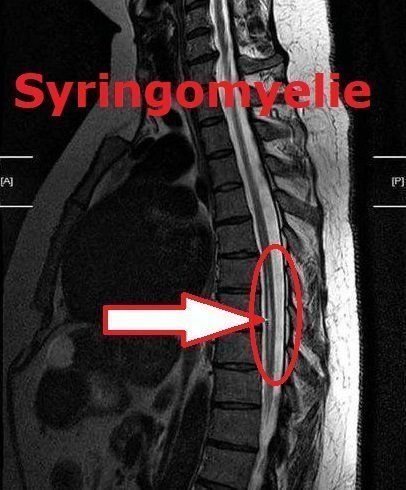

Syringomyélie

Syringomyelia (grec: syrinx = flûte, cavité, myelon = moelle, ici: moelle épinière) est une cavité dans la moelle épinière. Pour de nombreuses personnes, la maladie est associée à une douleur et à des sensations anormales dans différentes parties du corps à l'extérieur de la tête, selon l'endroit de la moelle épinière où se trouve la formation de la grotte (syrinx). Si le syrinx est très haut dans la moelle cervicale ou s'il existe également une hydrocéphalie (trouble du drainage du liquide cérébral) ou une malformation (Arnold) Chiari (une malformation de la fosse postérieure), des maux de tête peuvent également survenir.

Les photos des deux diagnostics «Malformation de Chiari» et «Syringomyélie» ont été aimablement mises à ma disposition par les personnes concernées pour ma page d'accueil. Ils sont à titre indicatif seulement! Vous pouvez voir le rétrécissement de la malformation de Chiari et la cavitation de la moelle épinière sur les deux images de syringomyélie.